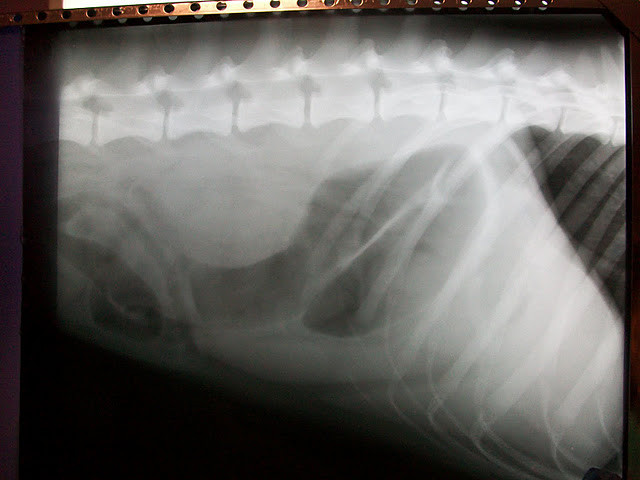

Les radios ont montré qu'il avait le début de l'intestin inflammé et beaucoup de gaz, le diagnostique était une gastrite hémorragique.

Dans le rapport il est dit qu'il est arrivé avec un épanchement pleural et des muqueuses pré-ictériques et que le diagnostic est en faveur d'un hémothorax secondaire à l'ingestion d'un produit toxique.

Le traitement mis en place donne une évolution positive au 14/11/2011